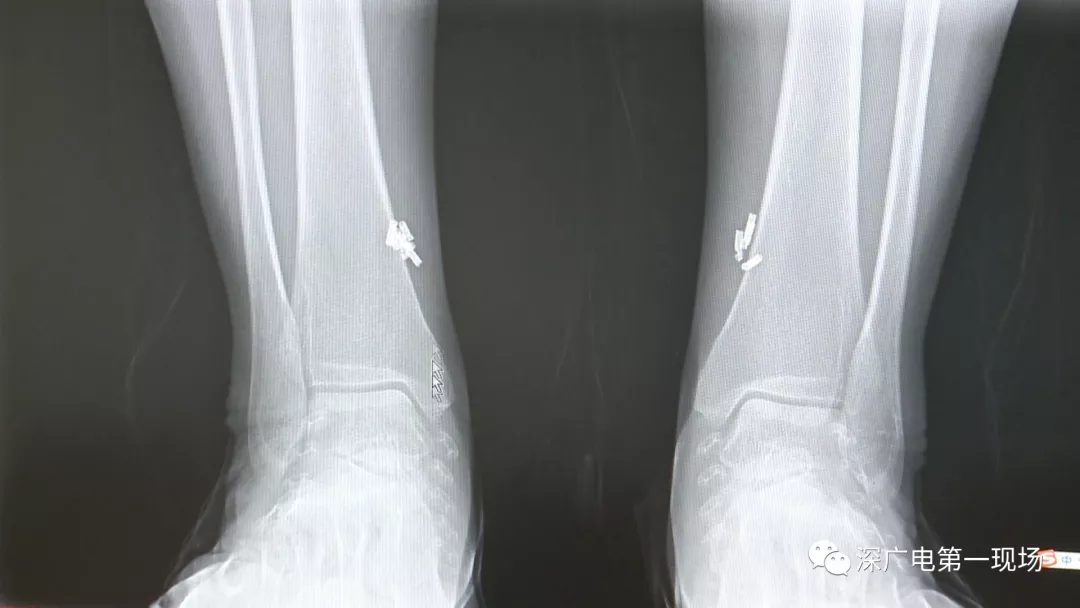

多方打聽之后,在山東某診所用全身埋彈簧圈的方式治療癲癇。陶主任介紹,這樣的方式想要治愈,那幾率也等同于撞大運啊!

陶醫(yī)生介紹,目前并沒有看到一個特別正規(guī)的報道,說這種方法到底治了多少病人,總體的治愈率是多少,有多少病人能夠發(fā)作減輕,這個是沒有看到。